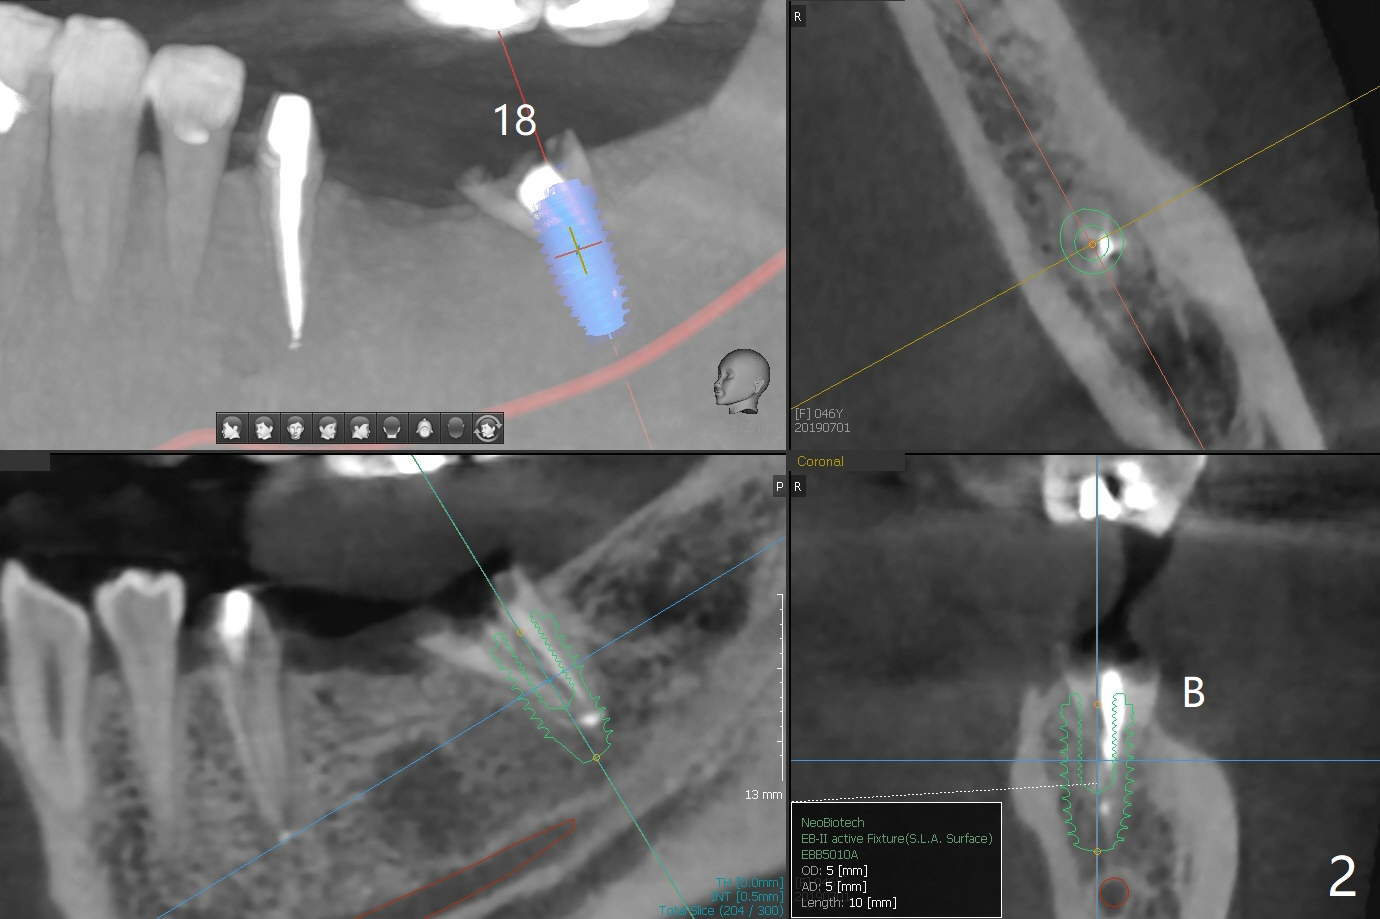

A 46-year-old woman has a failed FPD 18-20 (Fig.1). To have thicker buccal bone, the 5 mm implants at #18 (Fig.2) and 19 (Fig.3) seem to be a little large. Smaller (4.5 mm) will be more appropriate so that the coronal threads of the implant at #18 will be more securely covered by the regenerating bone. In the same manner, the implant to be placed in the healed site of #19 will have more buccal bone when the diameter of the implant reduces.